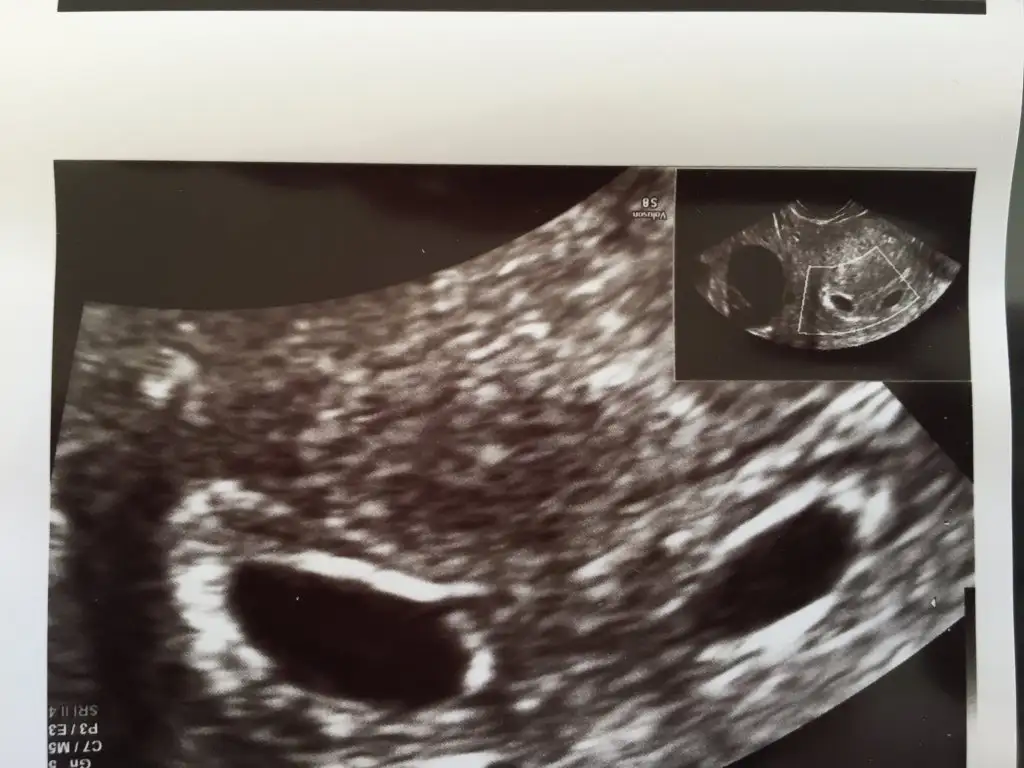

İkizlere hamileymişim :))) daha kalp atışlarını duymadık 15 eylülde çağırdı Allahım hayırlısıyla kalp atışlarını da duyarsak derin bi ohhh çekicem